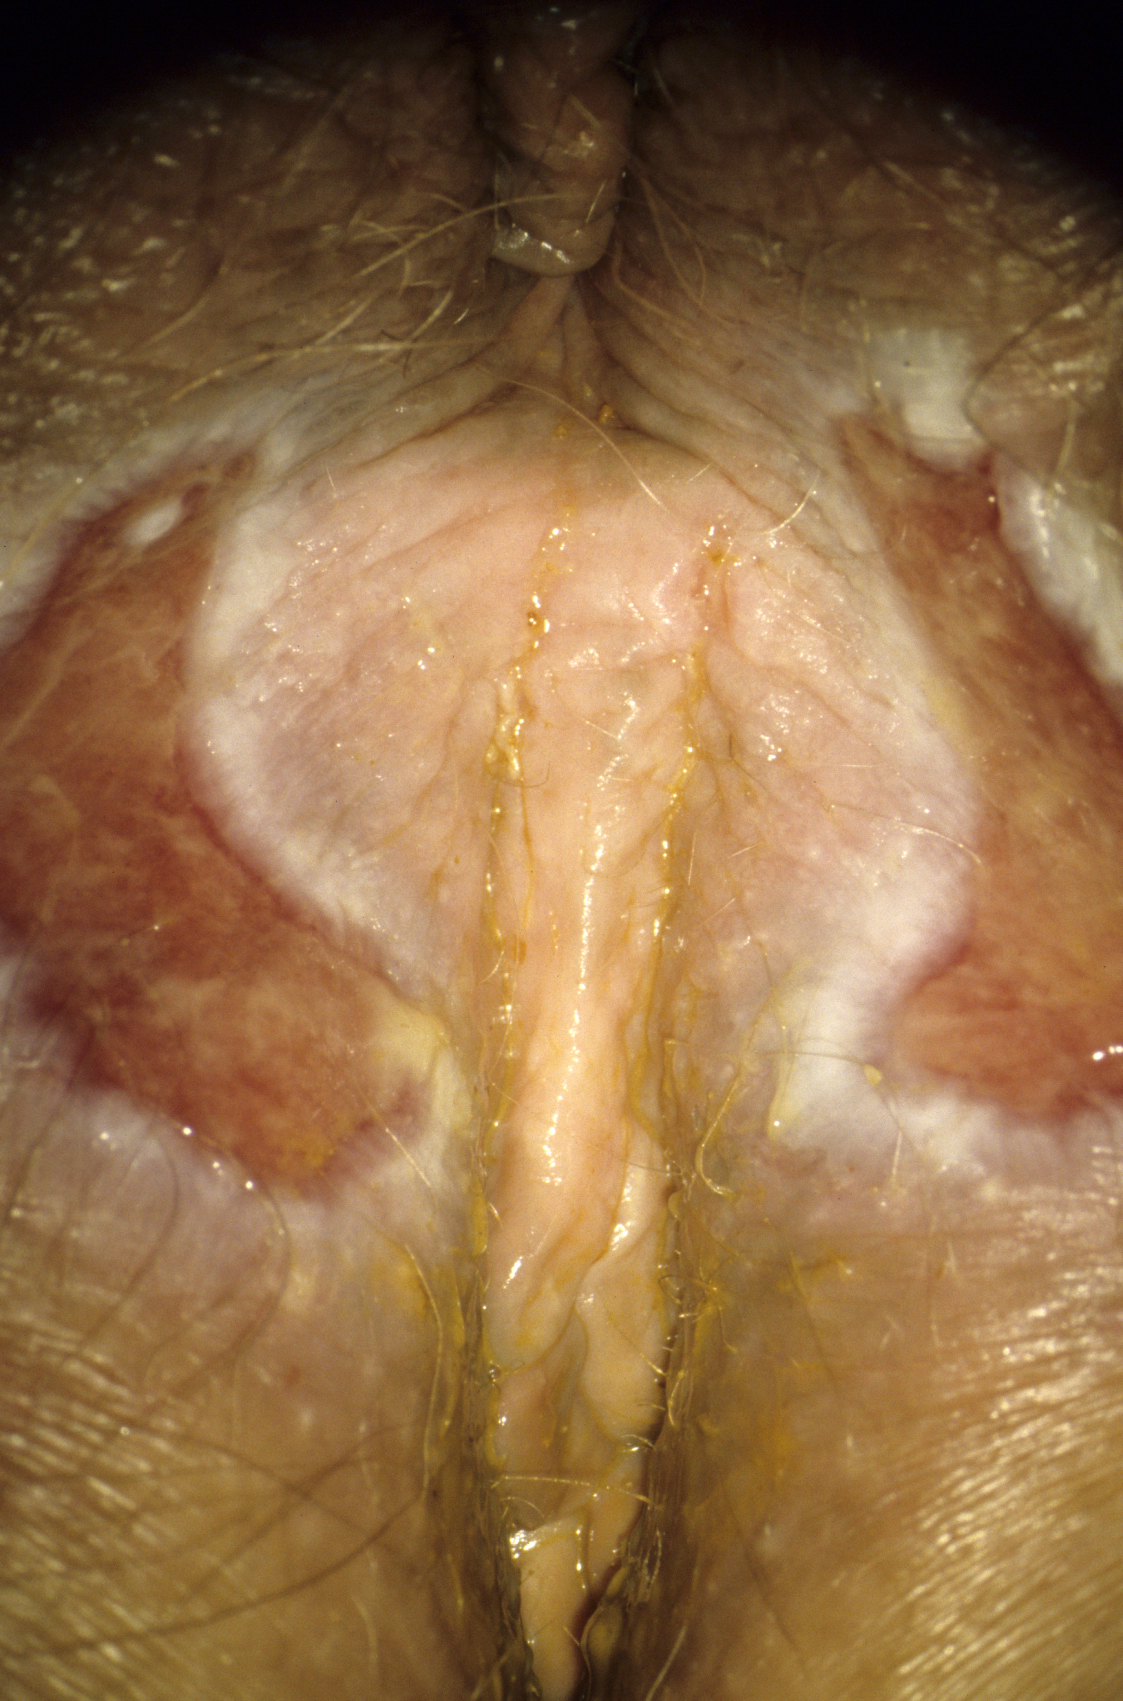

Atrophic diseases

With increasing age declining estrogen levels cause atrophy in the urogenital region, which can lead to a variety of symptoms. The skin is thinner, more sensitive and vulnerable due to smaller epithelial cells. This causes an increased susceptibility to urinary tract infections, dyspareunia and skin injuries (Figure 9). Atrophy can also occur in adolescent women with low estrogen receptor density or low-dose ovulation inhibitors.

Figure 9: Atrophia with bleeding into the urethral opening in a 60-year-old women (© Eiko Petersen)

The local administration of estrogens, mainly estriol, is a remedy, small amounts being often sufficient.